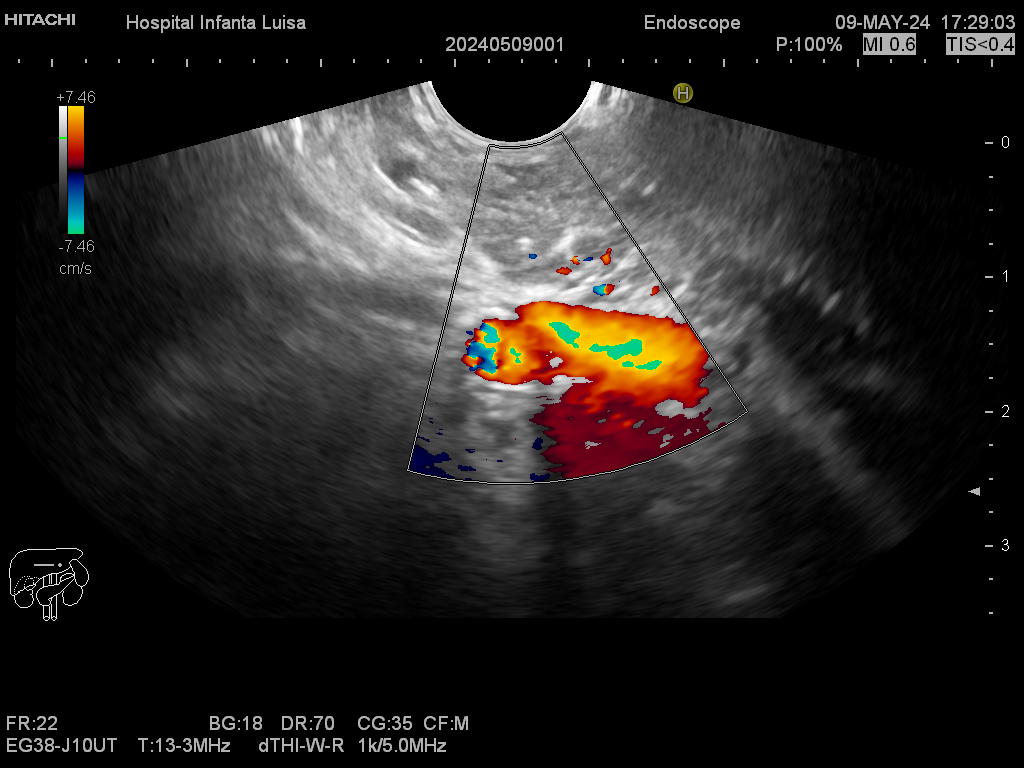

La Ecoendoscopia o Ultrasonografía endoscópica (USE) consiste en la exploración del tracto digestivo superior (principalmente), o de los últimos centímetros del tracto digestivo inferior (recto, generalmente), con un tipo de endoscopio especial que se llama ecoendoscopio.

La Ecoendoscopia, como su nombre indica, combina dos tipos de técnicas: la endoscopia y la ecografía, pues nos aporta simultáneamente una visión endoscópica (similar, aunque no igual, a la alcanzada con el gastroscopio y el colonoscopio) y ecográfica, que permite la visualización y estudio de las estructuras que quedan por fuera y están en contacto con la pared del esófago, estómago, duodeno o colon.

Mediante dicha exploración se explora minuciosamente los tramos mencionados, permitiendo valorar distintas patologías como lesiones propias de la pared de estos órganos (determinado su profundidad y extensión), o lesiones que quedan en órganos anexos, pero por fuera, de ahí la importancia de la visualización ecográfica, como páncreas, mediastino, hígado, diferentes adenopatías o masas indeterminadas previamente, entre otros.

Igualmente, es una técnica básica hoy día en el estudio de todo tipo de lesiones pancreáticas, en la determinación de formaciones subepiteliales esofágicas, gástricas (más frecuentes) o duodenales, o en el estadiaje de patología tumoral a estos niveles. La Ecoendoscopia permite la toma de biopsias a estos niveles, con control endoscópico y ecográfico, siendo una técnica de gran rentabilidad diagnóstica y seguridad.